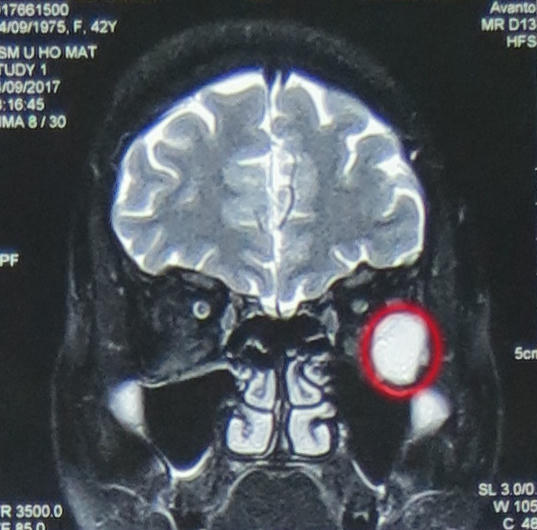

Với chẩn đoán u hốc mắt trái, kích thước 21x17x23mm, khối gây đè đẩy các cơ vận nhãn, nhãn cầu và dây thần kinh thị giác vào trong làm lồi nhãn cầu trái độ I, các bác sỹ khoa Phẫu thuật Thần kinh I đã hội chẩn và tiến hành phẫu thuật nội soi cắt u hốc mắt qua đường mũi.